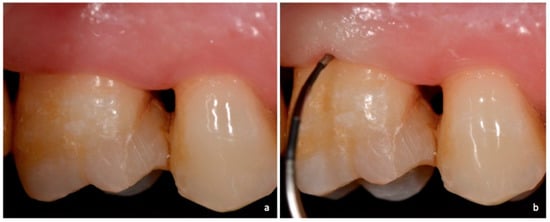

Figure 4. Non-exposed furcation lesion—Class II (NEII): (a) Second mandibular molar; (b) Buccal furcation lesion. Horizontal attachment loss of 4 mm.

Class II: partial horizontal bone loss. The examiner probe penetrates three millimeters or more from the entrance of furcation, but there is not a total attachment loss with a through and through opening of the furcation (Figure 4 and Figure 8).